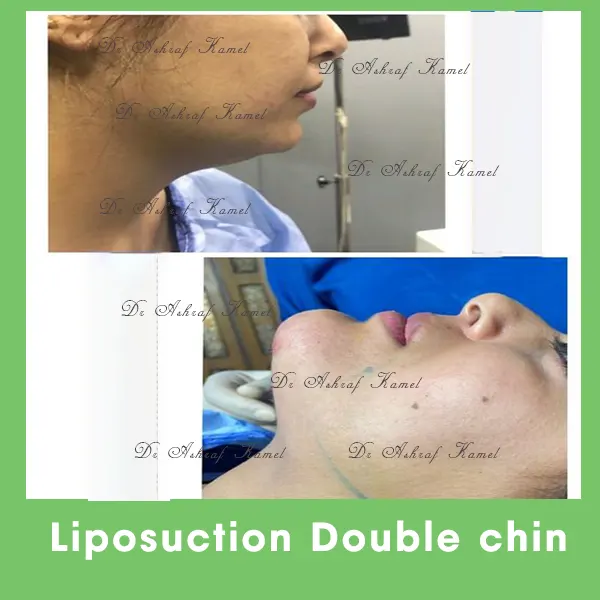

صور حالات مرضى

الخدمات

اشتهر بتقديم احدث تقنيات طب التجميل والجراحات التجميلية وعمليات تنسيق القوام، تكبير وتصغير وشد الثدي وتجميل الأنف وعلاج الترهلات، شد الذراعين و ازالة الترهلات، رفع الأرداف و علاج جراحات السمنة ونحت العضلات والـ6 باكس عالي التحديد، شفط الدهون بالفيزر والجي بلازما واحدث التقنيات بالخريطة الالكترونية، تجميل الجفون، تجميل الاذن وعلاج الاذن الوطواطية.